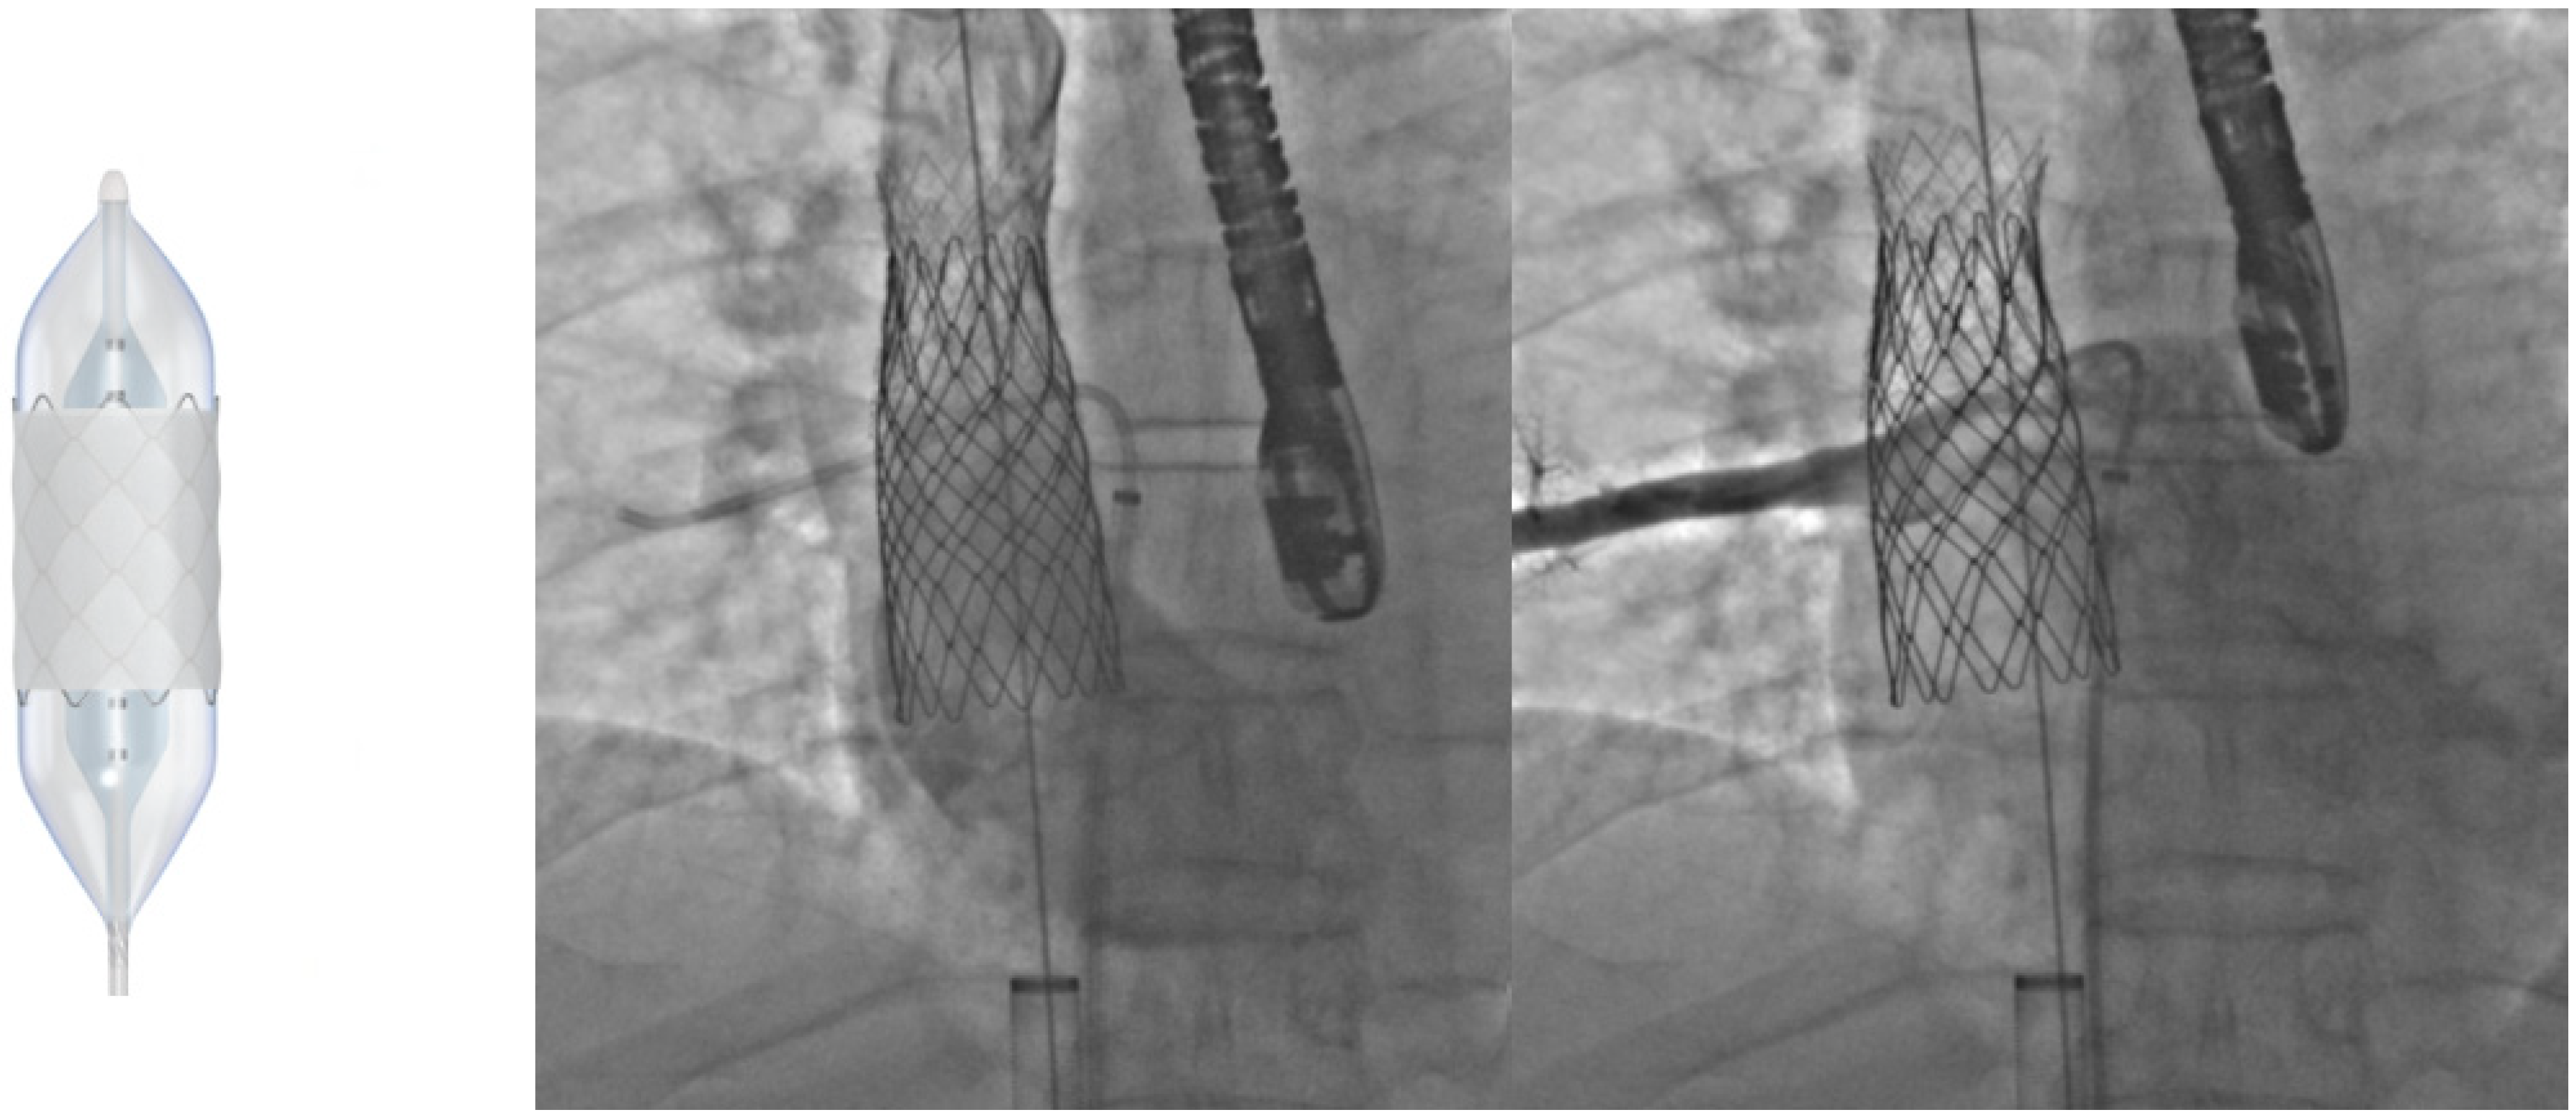

6. Transcatheter Pulmonary Valve Replacement (TCPVR)

- McElhinney, D.B.; Hennesen, J.T. The Melody® valve and Ensemble® delivery system for transcatheter pulmonary valve replacement. Ann. N. Y Acad. Sci. 2013, 1291, 77–85. [Google Scholar] [CrossRef]

- Alkashkari, W.; Alsubei, A.; Hijazi, Z.M. Transcatheter Pulmonary Valve Replacement: Current State of Art. Curr. Cardiol. Rep. 2018, 20, 27. [Google Scholar] [CrossRef]

- Bonhoeffer, P.; Boudjemline, Y.; Saliba, Z.; Merckx, J.; Aggoun, Y.; Bonnet, D.; Acar, P.; Le Bidois, J.; Sidi, D.; Kachaner, J. Percutaneous replacement of pulmonary valve in a right-ventricle to pulmonary-artery prosthetic conduit with valve dysfunction. Lancet 2000, 356, 1403–1405. [Google Scholar] [CrossRef]

- Gillespie, M.J.; McElhinney, D.B.; Jones, T.K.; Levi, D.S.; Asnes, J.; Gray, R.G.; Cabalka, A.K.; Fujimoto, K.; Qureshi, A.M.; Justino, H.; et al. 1-Year Outcomes in a Pooled Cohort of Harmony Transcatheter Pulmonary Valve Clinical Trial Participants. JACC Cardiovasc. Interv. 2023, 16, 1917–1928. [Google Scholar] [CrossRef] [PubMed]

- Patel, N.D.; Levi, D.S.; Cheatham, J.P.; Qureshi, S.A.; Shahanavaz, S.; Zahn, E.M. Transcatheter Pulmonary Valve Replacement: A Review of Current Valve Technologies. J. Soc. Cardiovasc. Angiogr. Interv. 2022, 1, 100452. [Google Scholar] [CrossRef]

- Morgan, G.; Prachasilchai, P.; Promphan, W.; Rosenthal, E.; Sivakumar, K.; Kappanayil, M.; Sakidjan, I.; Walsh, K.P.; Kenny, D.; Thomson, J.; et al. Medium-term results of percutaneous pulmonary valve implantation using the Venus P-valve: International experience. EuroIntervention J. Eur. Collab. Work. Group. Interv. Cardiol. Eur. Soc. Cardiol. 2019, 14, 1363–1370. [Google Scholar] [CrossRef] [PubMed]

- Garay, F.; Pan, X.; Zhang, Y.J.; Wang, C.; Springmuller, D. Early experience with the Venus p-valve for percutaneous pulmonary valve implantation in native outflow tract. Neth. Heart J. 2017, 25, 76–81. [Google Scholar] [CrossRef]

- Lee, S.Y.; Kim, G.B.; Kim, S.H.; Jang, S.I.; Choi, J.Y.; Kang, I.S.; Kim, Y.H. Mid-term outcomes of the Pulsta transcatheter pulmonary valve for the native right ventricular outflow tract. Catheter. Cardiovasc. Interv. 2021, 98, E724–E732. [Google Scholar] [CrossRef]